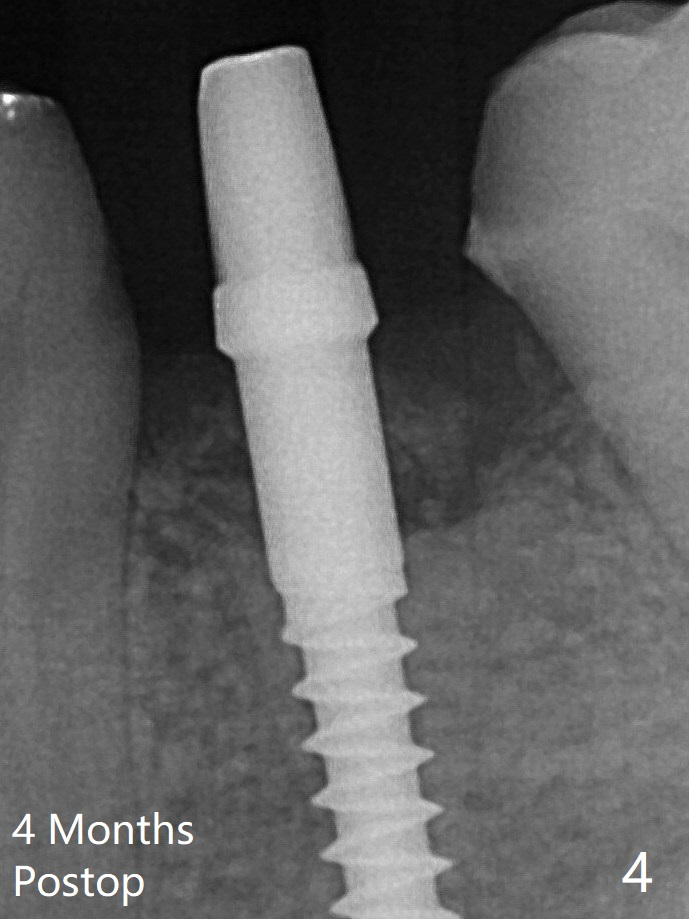

With the implant placed a little deeper (Fig.3 arrow), bone graft is placed (*), followed by suture. There is no bone loss with retention of bone graft 4 months postop; after reprep of the neighboring teeth, impression is taken (Fig.4). The three crowns are cemented 4.5 months postop (Fig.5).